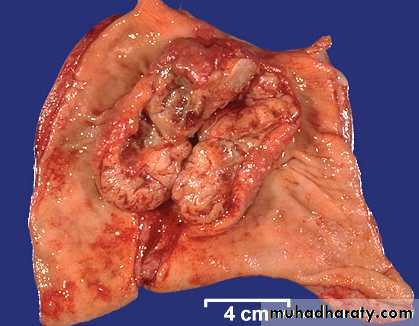

Morphologic types of carcinoma of the stomach

Fungating

UlceratingDiffuse

Fungating Carcinoma Stomach

Ulcerating Gastric Carcinoma